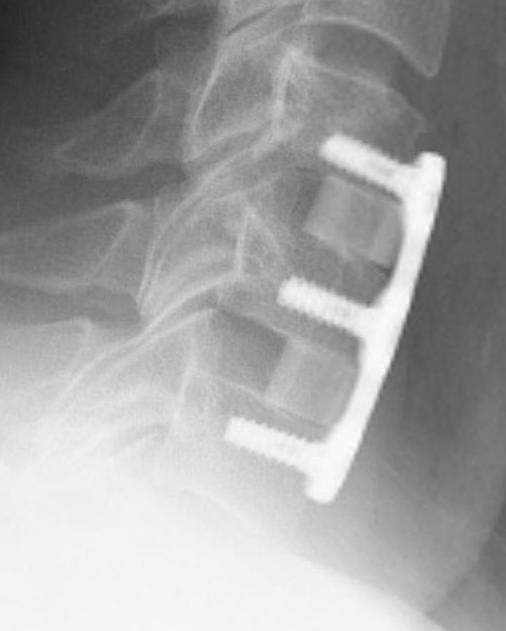

ACDF

Indication

Anterior cord compression

Single or double level compression

Kyphotic deformity

Advantages

Removes entire disc

Maintain / restore lordosis

Complications

Postoperative instability / kyphosis

- > 50% facet resection

- avoid by fusion or laminoplasty

Progressive kyphotic deformity

Associated with posterior approach without fusion